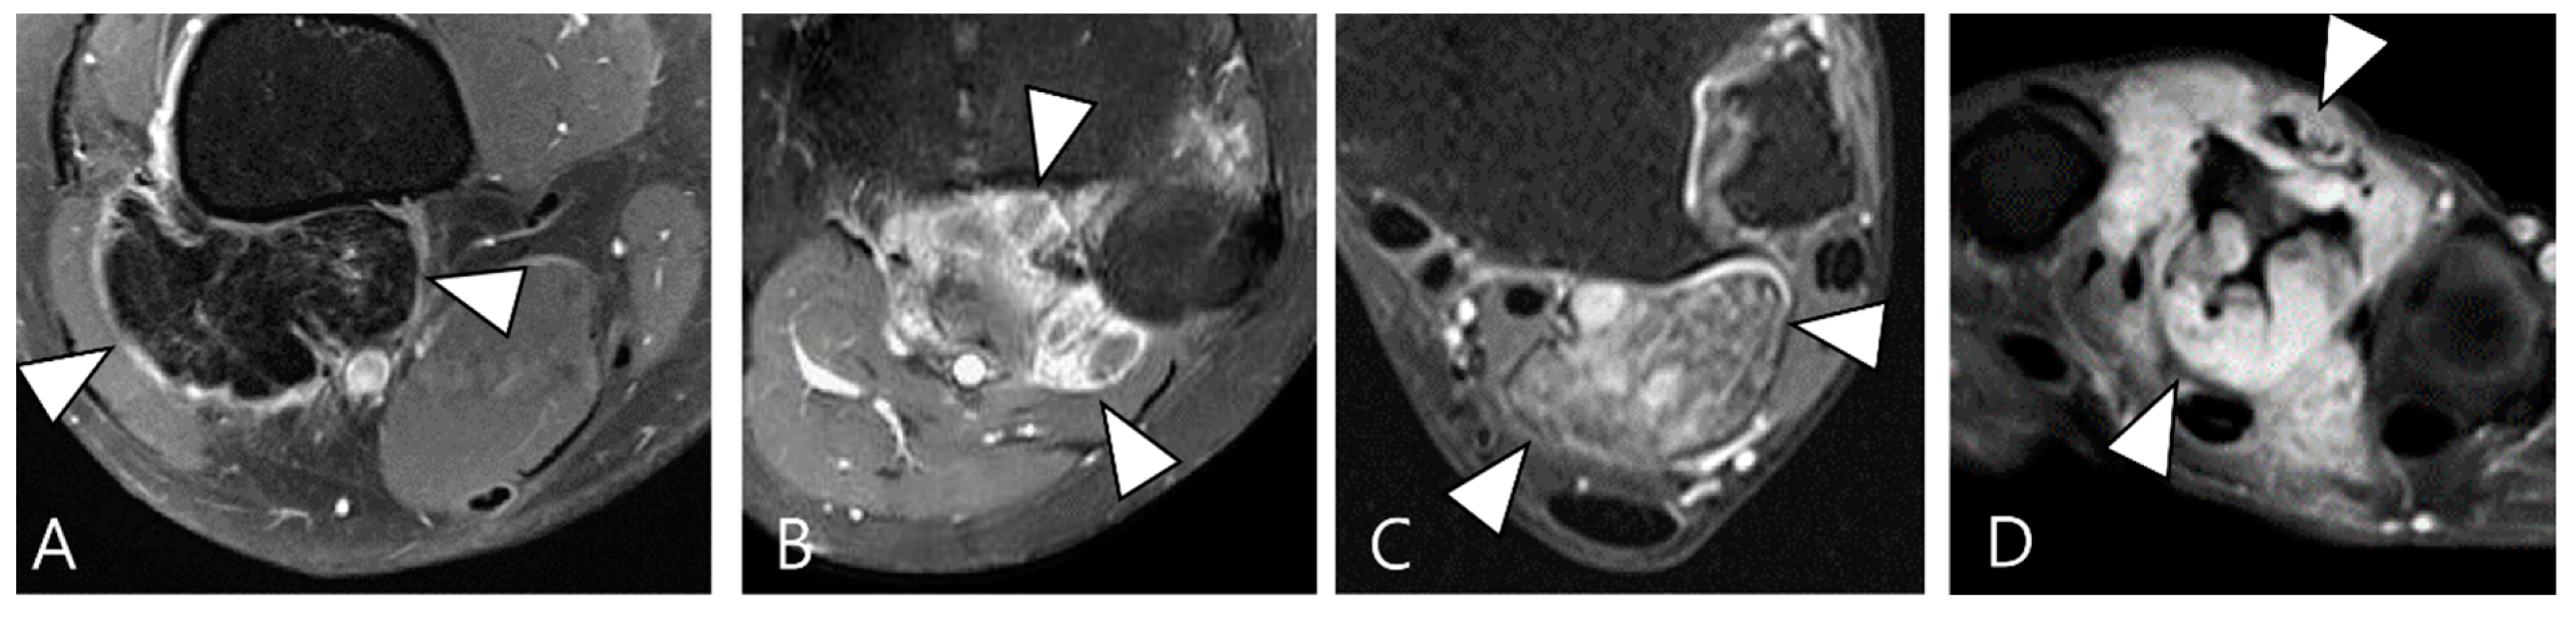

2.3. Morphological Findings for D-TSGCT

2.4. Relationship to Adjacent Structures of D-TSGCT

3.2. Differential Diagnoses of Extra-Articular D-TSGCT